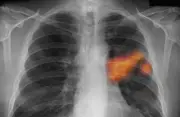

- الاكتشاف المبكر للأمراض المزمنة مثل السكري وأمراض القلب والسرطان، مما يزيد من فرص العلاج الناجح.